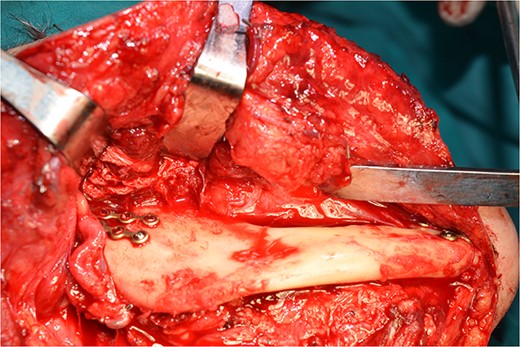

Operatively, after induction to general anaesthesia via orotracheal intubation, an extended submandibular incision to the right of the neck was performed and the mandible was revealed. The marginal branch of the facial nerve was recognized and protected. Following this, the double osteotomy of the mandible was performed in the parasymphysis—with preplating of two miniplates with four holes—and in the subcondylar area—with preplating of two miniplates with four holes (Figs 3 and 4). The mandibular ‘swing’ that was performed straight after that (Fig. 5) gave space for the dissection of the CCA and the bifurcation. All the branches were prepared, and the aneurysm was accessed (Fig. 6). The reconstruction was achieved by bypassing the aneurysm, trans-positioning of the right ECA and end-to-end anastomosis of the ECA with the healthy peripheral end of the ICA near the skull base, after the lignification of the peripheral end of the ECA and its smaller branches (Fig. 7). The anastomoses were checked for leakage (Fig. 8), the mandible was reduced and the easily fixated rigidly after preplating (Fig. 9).

The step before the end-to-end anastomosis of the external carotid artery with the healthy peripheral end of the internal carotid near to the skull base.